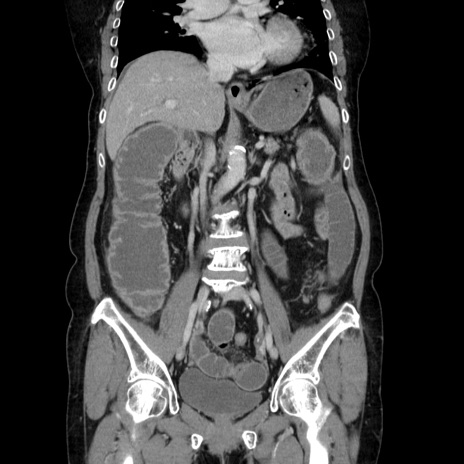

症例5(冠状断像)

【症例】70歳代女性

【主訴】お腹が張る

【現病歴】1週間くらい前から腹部膨満の自覚あり。昨日夜から増悪したため、本日救急外来受診。

【身体所見】意識清明、BT 36.5℃、BP 165/106mmHg、HR 80bpm、SpO2 98%、腹部:膨満、軟、自発痛・圧痛なし、触診にて不快感あり、腸蠕動音:減弱

【データ】WBC 12600、CRP 1.04